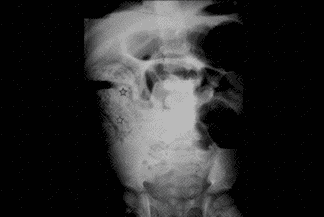

Texto alternativo para a imagem Créditos: Dra. Elazir Mota - Rio de Janeiro/RJ

Descrição da figura: Radiografia de abdome AP em ortostase evidencia importante distensão de algumas alças de delgado, ausência de gás no reto e a clássica imagem em "miolo de pão" (asteriscos), compatível com obstrução intestinal por infestação de Ascaris lumbricoides .

• Radiografia de abdome: Para avaliar a presença ou não de obstrução intestinal. Quando há infestação por Ascaris , observamos a presença da clássica imagem em "miolo de pão" (figura acima) ;